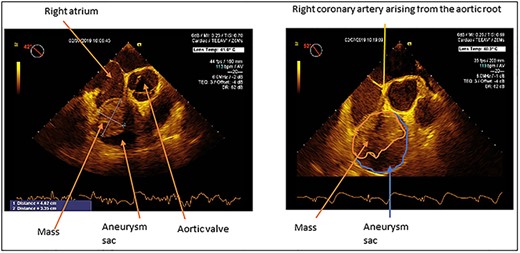

Transoesophageal echo demonstrating RCA aneurysm with a mass partially filling the aneurysm sac. The size of the mass is 4.62 by 3.35 cm. The proximal RCA is seen originating from the aortic root.

Transoesophageal echo was performed at the initiation of anaesthesia. This confirmed the dilation of the RCA, and that there was a mass within the dilation, see Fig. 3. The lumen of the RCA was visible running through the mass that partially filled the aneurysm sac.